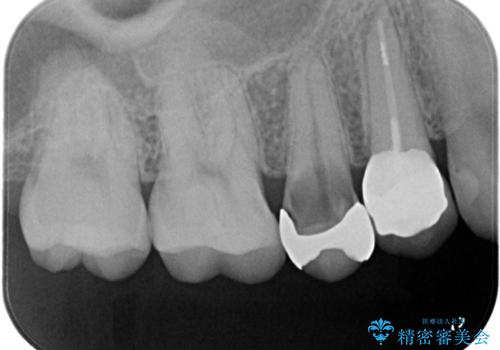

右上5番に保険適応のインレーが入っている歯がインレーを境に2つに割れてしまっていました。

右上5番の口蓋側歯質が失われ、露出した歯質内面は軟化象牙質を除去していく過程で露髄する可能性が大きくありました。患者さんには生活歯髄療法と抜髄のどちらかになると説明し、生活歯髄療法の適応と判断し行いました。

補綴物は残存歯質量からクラウンとしました。